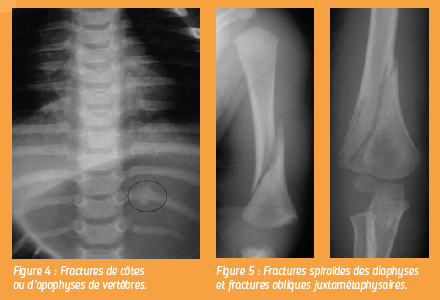

Les lésions atteignent la « virole périchondrale » qui est une zone de fragilité particulière à la jonction entre le cartilage de croissance et l’os métaphysaire.

Ces fractures sont difficiles à identifier et nécessitent une technique rigoureuse et un oeil expert. Les fractures de côtes ou d’apophyses de vertèbres sont pratiquement synonymes d’enfant battu en dehors d’un polytraumatisme connu.

Les fractures spiroïdes des diaphyses et les fractures obliques juxtamétaphysaires du jeune enfant doivent être considérées comme suspectes en l’absence de corrélation précise avec un traumatisme.